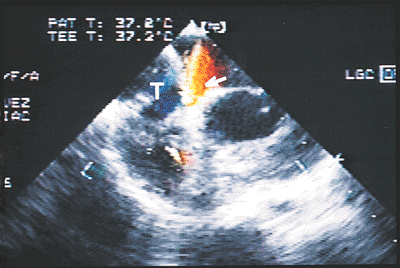

FIGURE 8.2.40. Fontan-type surgery. Transverse plane image at the level of the atrial septum shows the integrity of the tunnel wall (T). Red and yellow represent a flow greater than expected through the obligatory atrial septal defect (arrow)

FIGURE 8.2.41. Fontan-type procedure. A. High short-axis view in a patient with total cavopulmonary deviation. There is a large defect, which permits a venoarterial shunt, in the wall of the intra-atrial patch or tunnel (T). B. Transesophageal echocardiogram in a patient with total cavopulmonary anastomosis and thrombosis of the atrial tunnel (T)